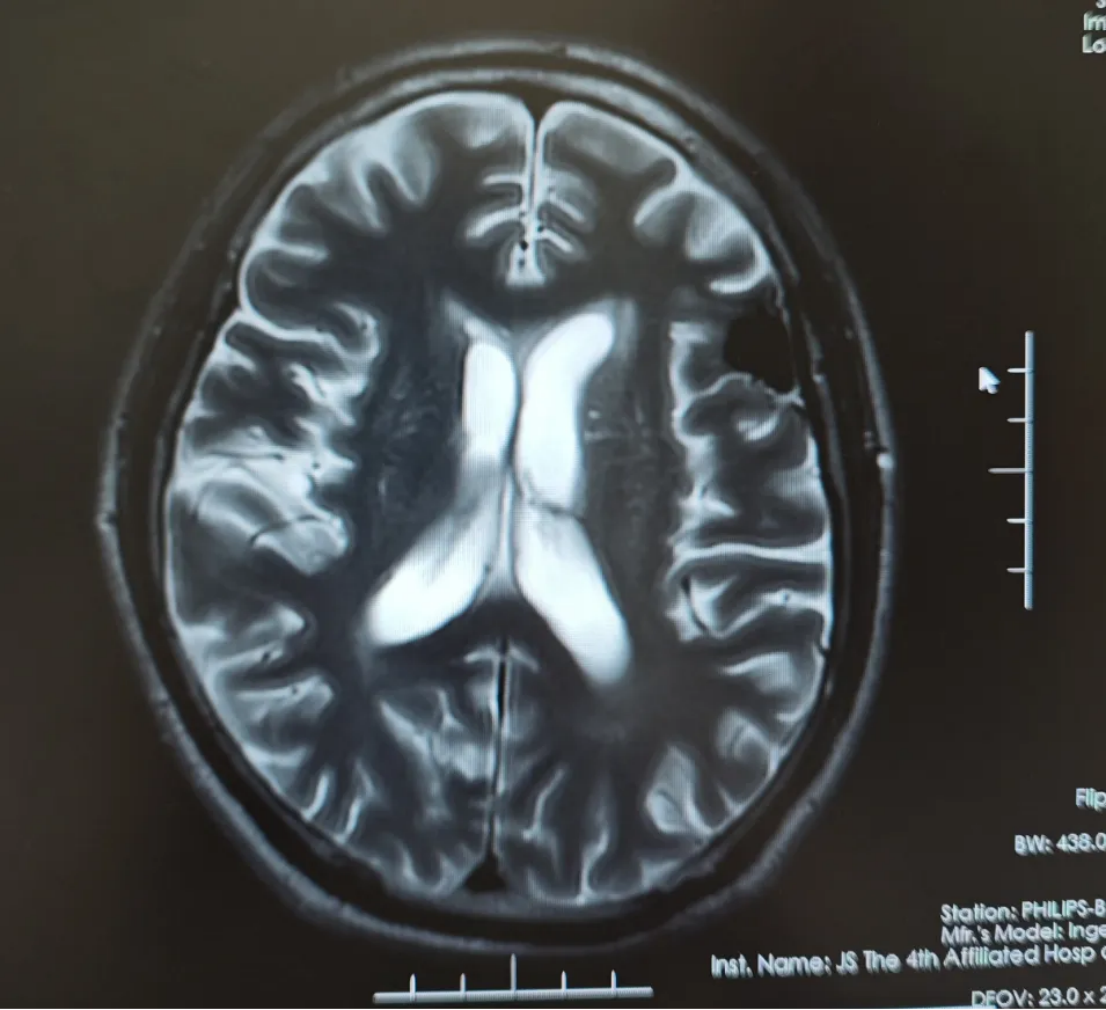

2023-08-15复查磁共振平扫+增强提示:左侧额叶占位性病变,大小约3.8cm*3.2cm *3.5cm团块状异常信号影,结合病史,考虑脑转移瘤;脑内多发缺血腔梗灶;老年性脑改变(图1)。

图1 复查磁共振平扫+增强